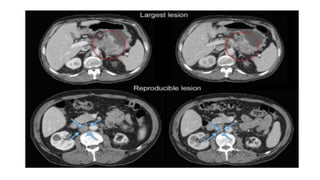

• #38 Largest lesion may not be most reproducible: most reproducible should be selected as target. In this example, the primary gastric lesion (circled at baseline and at follow-up in the top two images) may be able to be measured with thin section volumetric CT with the same degree of gastric distention at baseline and follow-up. However, this is potentially challenging to reproduce in a multicentre trial and if attempted should be done with careful imaging input and analysis. The most reproducible lesion is a lymph node (circled at baseline and at follow-up in the bottom two images).